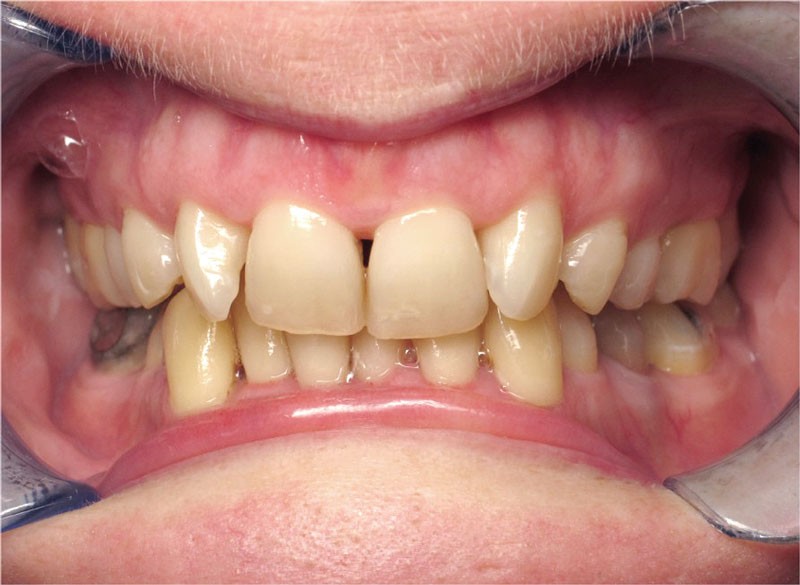

La patiente donne son accord pour un appareillage Damon Insignia métal qui permet une individualisation complète des brackets dans les 3 sens de l’espace.

Un appareillage Damon métal a été mis en place, réalisé à partir d’un set up numérique Insignia pour obtenir un contrôle précis des torques et de la forme d’arcade et réduire le temps de finition grâce à un collage indirect très précis.

Les objectifs de traitement ont été remplis. Nous avons observé un excellent contrôle du torque et une absence de perte de l’occlusion postérieure grâce à la technique Insignia.